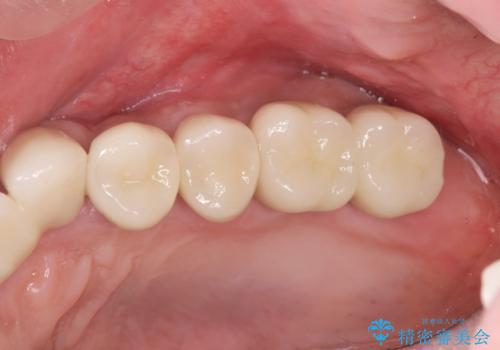

骨の造成を行った上顎インプラント治療

骨の造成を行ったことで歯肉のラインは平らになり、清掃性の高い歯周環境を作り出すことができました。